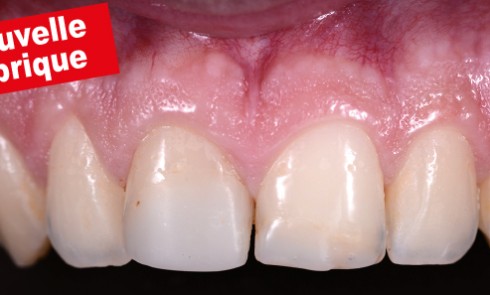

Article réservé à nos abonnés Réalisation d’un composite antérieur

Le matériel   Du projet au champ opératoire   Adhésion et stratification initiale Après la dépose des anciennes restaurations les...